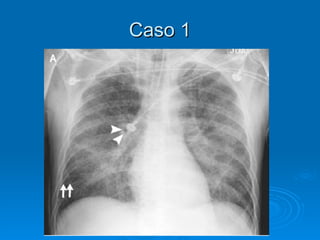

Caso 1 Pcte de 65 anos internada na terceirinha devido a um linfoma esplênico começa a cursar com dispnéia importante logo após terminar de receber 3 CGVs. Ao exame físico, apresenta estertores difusos em AHT. Como o Rx de tórax pode ajudar a diferenciar entre um edema não-cardiogênico por TRALI de um edema cardiogênico secundário a infusão excessiva de volume?

Caso 1 Pctede 65 anos internada na terceirinha devido a um linfoma esplênico começa a cursar com dispnéia importante logo após terminar de receber 3 CGVs. Ao exame físico, apresenta estertores difusos em AHT. Como o Rx de tórax pode ajudar a diferenciar entre um edema não-cardiogênico por TRALI de um edema cardiogênico secundário a infusão excessiva de volume?